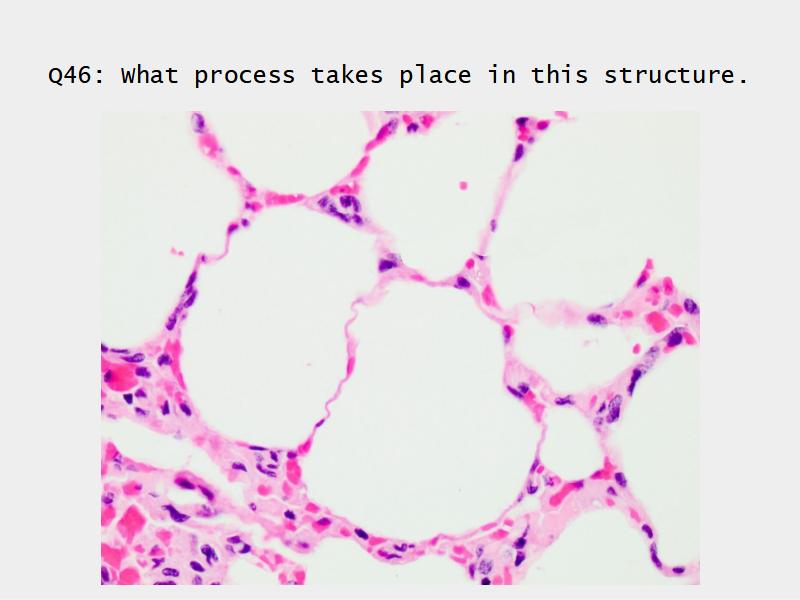

- Make gas exchange possible

What cells are present?

Components of the Blood-Air Barrier?

- Alveoli